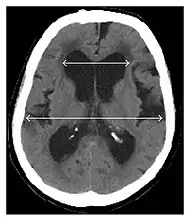

- Imaging from magnetic resonance imaging (MRI) or computed tomography (CT) is needed to demonstrate enlarged ventricles and no macroscopic obstruction to cerebrospinal fluid flow. Imaging should show an enlargement to at least one of the temporal horns of lateral ventricles, and impingement against the falx cerebri resulting in a callosal angle ≤ 90° on the coronal view, showing evidence of altered brain water content, or normal active flow (which is referred to as "flow void") at the cerebral aqueduct and fourth ventricle.

MRI scans are preferred. The distinction between normal and enlarged ventricular size by cerebral atrophy is difficult to ascertain. Up to 80% of cases are unrecognized and untreated due to difficulty of diagnosis.[7] Imaging should also reveal the absence of any cerebral mass lesions or any signs of obstructions. Although all patients with NPH have enlarged ventricles, not all elderly patients with enlarged ventricles have primary NPH. Cerebral atrophy can cause enlarged ventricles, as well, and is referred to as hydrocephalus ex vacuo.